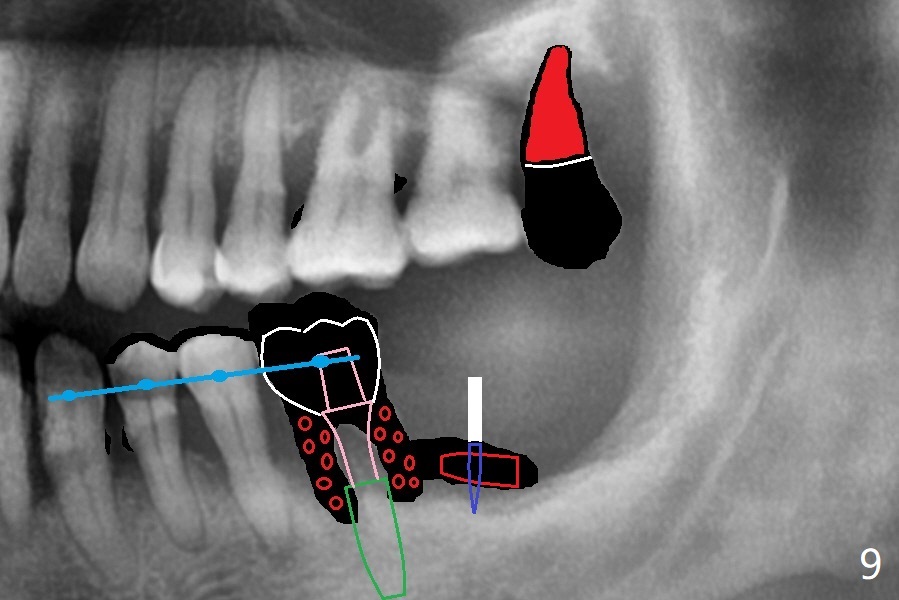

56岁男几十年拒绝牙周炎治疗,也不愿意拔除所有牙齿做全口植牙修复。17,18号牙自行脱落,现在要求拔除16,19;18,19种植(图一),后者牙龈厚(双箭头),但是18号牙骨质高度不足(图二),勉强植入5x7.3毫米植体。15,16骨质吸收严重(图三),16,19拔除,局部深洗后(图四:黑色),为了延长15号牙使用期,16号牙牙槽窝植骨(图五:红色)。19号牙种植徒手,因为邻牙(包括20,21号牙))松动,做导板不准确,钻洞使用环形钻头(图六),保留骨塞(bone plug),用于18号牙骨质高度骨块移植。19号牙拔除后,往远中18牙位做潜行分离(图七:黑色)。19种植(绿色),基台(粉红色),骨粉(圆圈),临时牙冠(白色),16号牙粘性骨粉植骨(红色),PRF,Cytoplast覆盖(白线),缝合。从19号牙钻洞取来的骨塞,塞入18号牙潜行分离处(图八);利用临时牙冠和22号牙以及钢丝,树脂固定20,21号牙(蓝色),并且降低咬合(*)。最后,用螺钉固定骨塞(图九:深蓝色)。